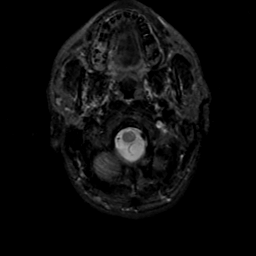

MR Study #19, August 25, 1991 -- Slice #2

[Home][Help][Clinical][Tour 1][Tour 2] Slice 2